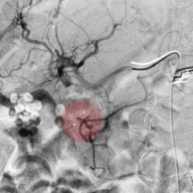

7. Embolisation – Verschluss von Gefäßen

Bei Blutungen durch Gefäßverletzungen, Gefäßmissbildungen, Tumorerkrankungen o. ä kann es sich in der Behandlung notwendig machen, Blutgefäße von innen zu verschließen. Dazu werden über Katheter am Ort des geplanten Gefäßverschlusses kleine Verschlusskörper, Verschlussspiralen oder verschließende Flüssigkeiten injiziert. Bei Tumoren ist auch die lokale Gabe von Chemotherapeutika möglich.